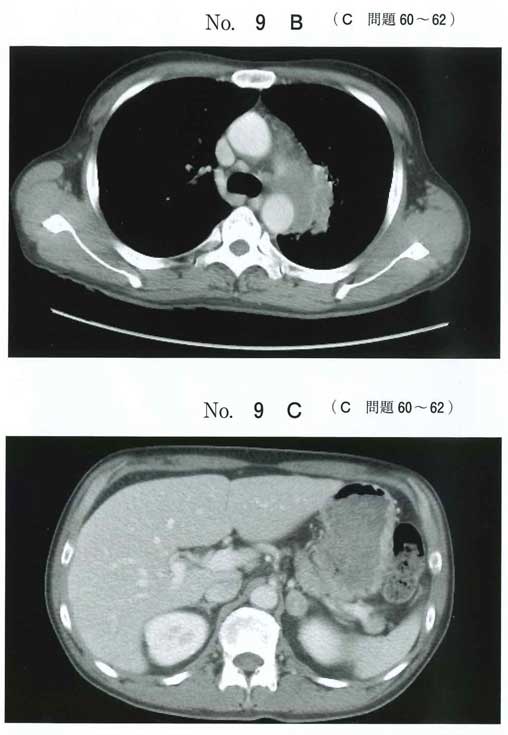

腹部CTは左の副腎に腺腫がありそうですが、肺癌転移の可能性も考慮しろってことですかね?

食思不振、倦怠感、低血圧、Na118、好酸球増多21%から副腎不全ぽいデータです。eCTで左副腎腫瘍ありそうです。左縦隔リンパ節腫脹とあわせると肺癌の副腎転移に伴う副腎不全でしょうか。ACTHとコルチゾールは必須ですが、SIADHの除外のためにレニンアルドステロンも提出してもいい気がします。(あとは副腎腫瘍の鑑別としてPAは上がるのでPAの除外のために)。治療はハイドロコートン点滴かと思います。